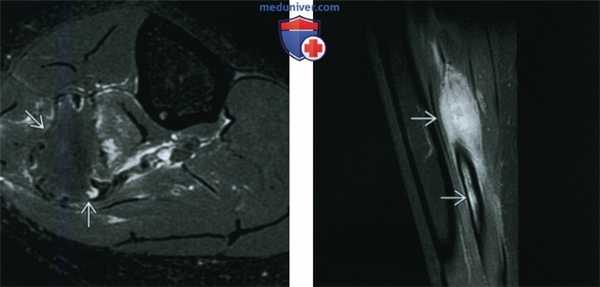

(Справа) МРТ, аксиальная проекция, режим Т1: внутрикостный очаг у этого же пациента В, характеризующийся сигналом, интенсивность которого немногим ниже сопряженной мышцы. Визуализируется выраженная вспученность малоберцовой кости. Такие признаки неспецифичны, однако сигнал очень низкой интенсивности предполагает наличие фиброзного очага.

• Режим Т1: низкая интенсивность сигнала (изо- или гипоинтен-сивный по отношению к мышце)

• Последовательности, чувствительные к жидкости (с подавлением или без подавления сигнала от жира): изо- или гипоинтенсивный сигнал по отношению к мышце:

о Сигнал низкой интенсивности в режиме Т2 охватывает не менее 50% очага

о Сигнал низкой интенсивности в режиме Т2 является наиболее значимым дифференциально-диагностическим признаком

о Может искажаться на фоне отека и кровоизлияния в зоне патологического перелома

• Контрастное усиление: неоднородное накопление контраста

(Слева) МРТ, аксиальная проекция, режим Т2, с подавлением сигнала от жира: у этого же пациента определяется область преимущественно низкоинтенсивного сигнала, окруженная зоной умеренно выраженного отека. Низкоинтенсивный сигнал занимает большую часть патологического очага. Десмопластическая фиброма является внутрикостной формой фиброматоза или мягкотканного десмоида. Такое новообразование встречается редко, его наличие можно предполагать при умеренно агрессивном костном очаге, большая часть которого имеет сигнал низкой интенсивности в режиме Т2.

(Справа) МРТ, сагиттальная проекция, режим Т1, с подавлением сигнала от жира и контрастированием, этот же пациент: очаге контрастным усилением.